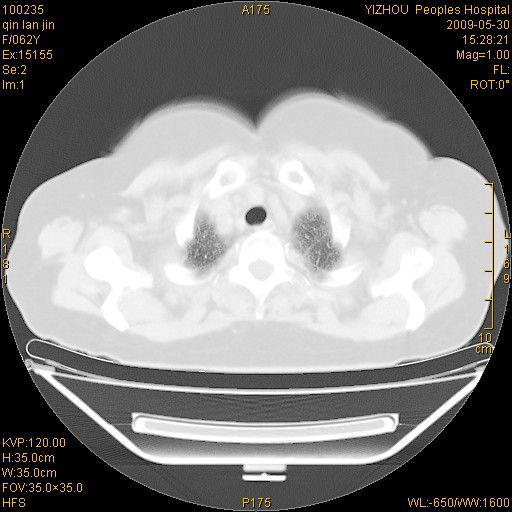

标题: CT20268:肺泡癌?间质性肺炎? [打印本页]

标题: CT20268:肺泡癌?间质性肺炎?

女,62岁,近二年经常咳嗽,近二个月,消瘦、乏力。

前面一张胸片是今天照的,后面一张胸片是去年9月份的。

弥漫性双肺间质纤维化。

两肺弥漫性间质性病变(间质性肺炎伴肺间质纤维化?)。

间质性肺炎伴肺间质纤维化。

纵隔淋巴结大,须排外癌性淋巴管炎